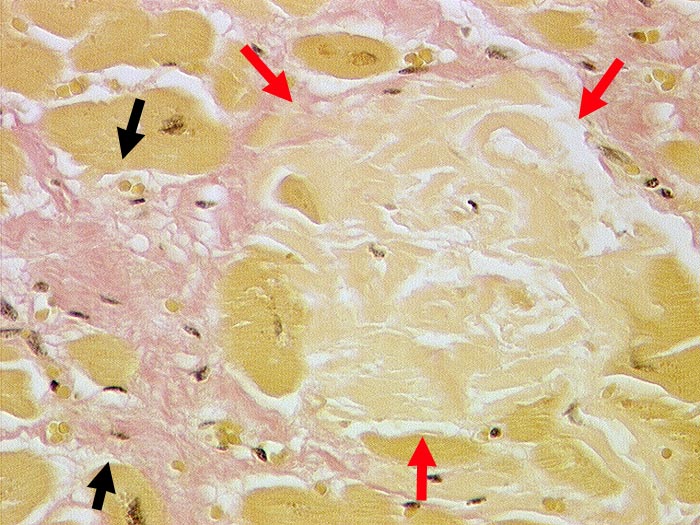

Senile Amyloidose des Myokards

Scholliges azelluläres Amyloid zwischen den Myokardfasern. Daneben feinfleckige Fibrose.

Koronare Herzkrankheit. Arterielle Hypertonie.